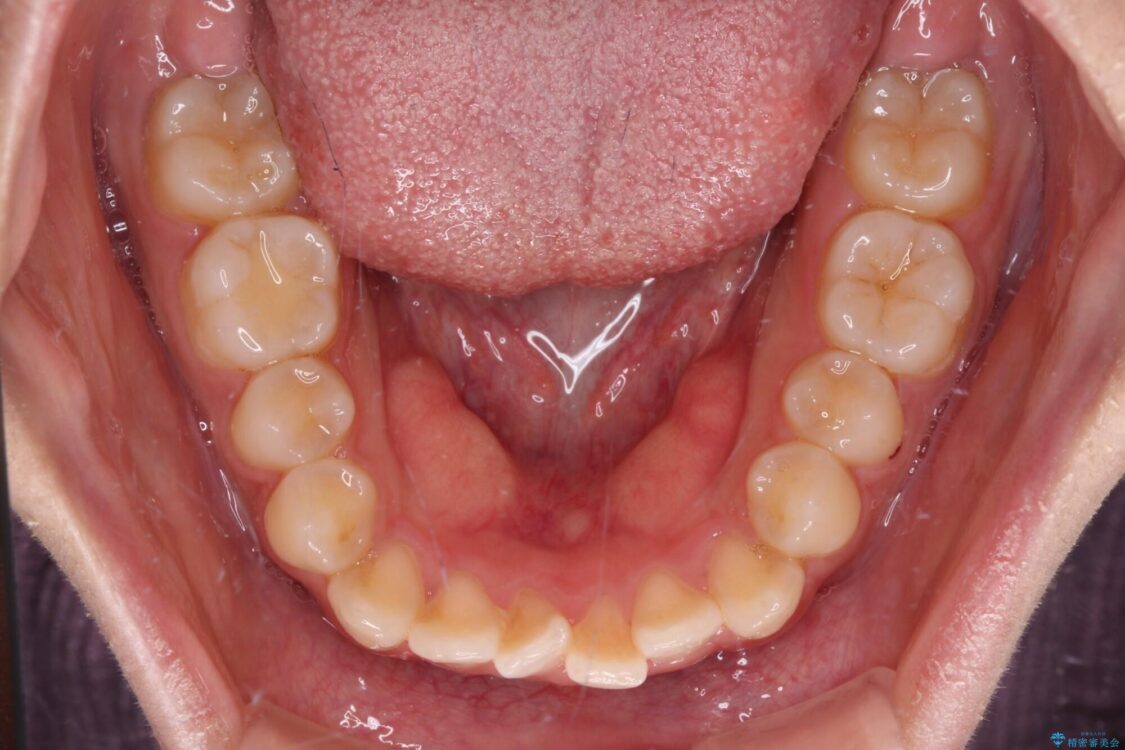

治療前

• 【モニター】短期間で終わりたい ワイヤー装置での非抜歯矯正 治療前画像

前歯のデコボコを気にして来院された患者様です。